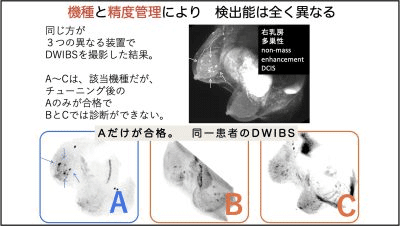

2つ目は、日本人に多いと言われる乳腺組織が多い高濃度乳房(デンスブレスト)の場合、がんが見えづらいという問題が解決していない点です。検出率が半分となるClass D(Class 4)の高濃度乳房は、最新のマンモ(トモシンセシス、3Dマンモ)でも解決できていません。また、ご自分が高濃度乳房かどうかを受診者が知らされないことも多いんです。

一般的には、拡散強調画像(DWI)の画質がとても悪いため、「そんな悪い画像で十分な診断ができるわけない」という医療関係者からの不信に悩みました。

それでも開発した自分はこの技術が優れていることを知っていましたし、自分自身だけが分かる精度の高め方、精度の保持のしかたがありましたから、批判されても勇気を持って進めていきました。その結果、PPV(陽性反応適中度)約20%という、従来の検診を遥かに超える成績を、乳腺外科の先生が次々に発表してくださり、手応えを感じています。